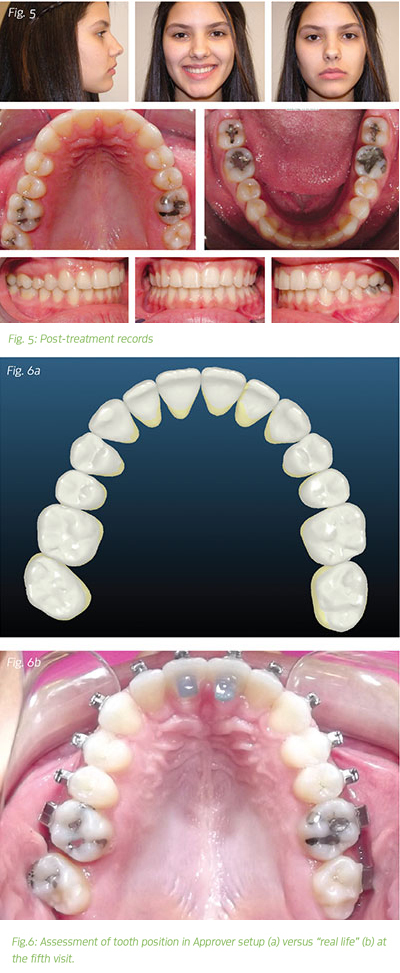

At the initial consultation, I had relayed to the family that I was confident the patient could be treated non-extraction to a pleasing result in 18 months. The actual treatment time was 11 months (in eight appointments including bonding, debonding and one emergency appointment). The efficiency of this customized appliance system in conjunction with bite turbos, lightforce wires and light CL II elastics resolved the crowding, overbite and overjet, and corrected the A/P and crossbite (Fig. 5).

At the interim panograph appointment, I review roots for possible bracket repositioning as well as assess whether there are any discrepancies between the digital Approver setup and the "real life" tooth positions (Fig. 6). To address discrepancies, I make a determination about whether the genesis of the issue was the Approver setup or bracket placement.